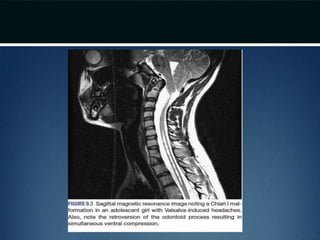

Chiari I Malformation •Theory: Difficulty in rapidly equilibriating the CSF pressure wave seen during the Valsalva maneuver • Prolonged intracranial hypertension relative to intraspinal compartment  downward migration of the cerebellar tonsils  obstruction of normal CSF flow from 4th ventricle to cervical subarachnoid space  CIM • Obstruction of Foramen of Magendie by arachnoid veils or septation might also lead to the same

Treatment • 10% patientswith CIM – associated hydrocephalus – CSF diversionary shunt or ETV as the initial form of therapy • Symptomatic ventral compression out of proportion to dorsal compression  ventral decompression (transoral odontoid resection)